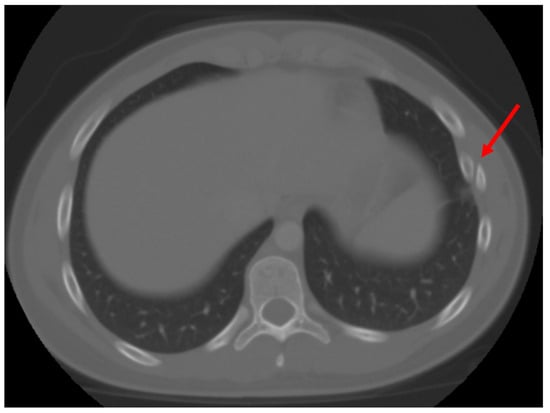

Figure 3.

Malunion fracture of the 4th rib. Red arrow points to the location of injury.